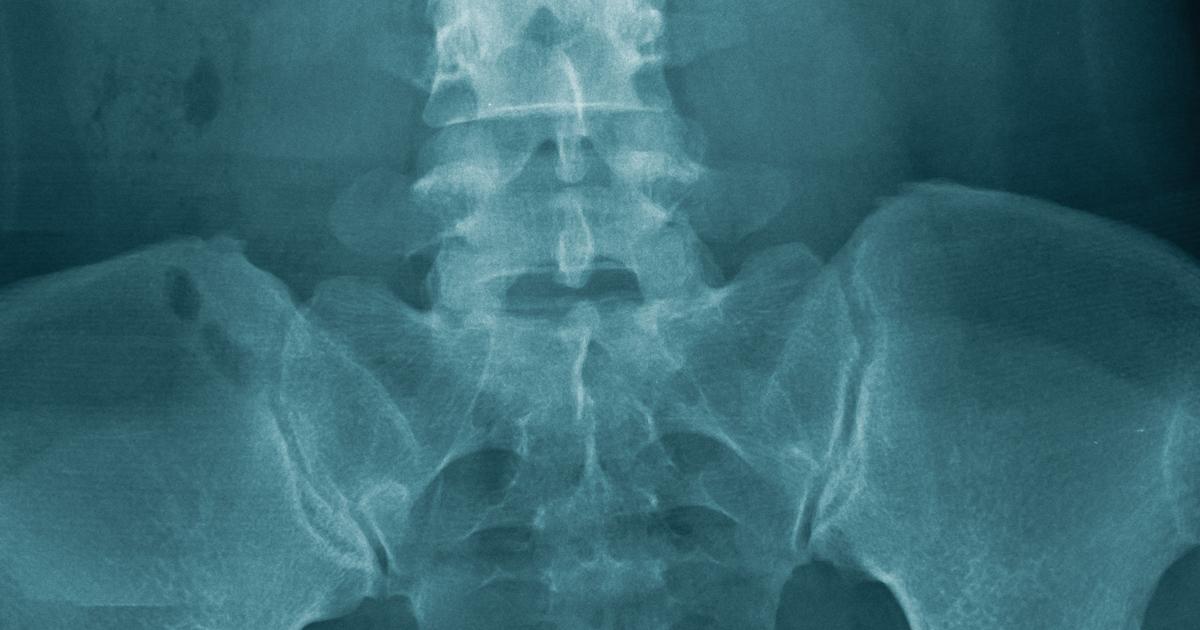

Sacroiliitis is a condition that causes inflammation to the sacroiliac joints. There are two sacroiliac joints, located at the point where the pelvis connects to the lower spine. For some individuals, only one joint is affected, while others have symptoms in both joints. Sacroiliitis isn't an inflammation of the coccyx, so it's not related to coccydynia. However, it can cause pain in the tailbone. The pain may also radiate through the lower back, buttocks, and one or both legs. If individuals stand for prolonged periods of time or climb stairs, they may find the pain becomes worse. It's often difficult to diagnose sacroiliitis because the symptoms can be mistaken for coccydynia or other conditions that cause lower back and tailbone pain. Sacroiliitis has been linked to certain diseases that lead to inflammation and arthritis in the spine.